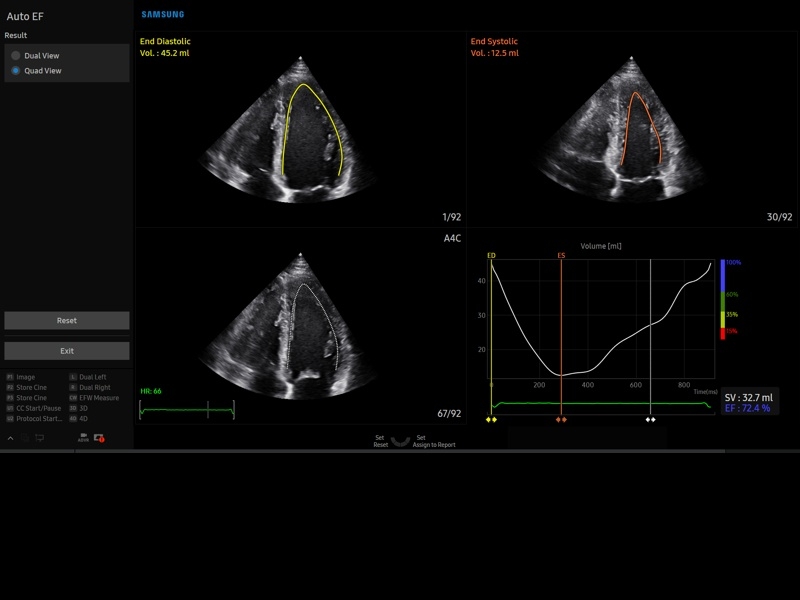

• Кардиологический пакет с функцией StressEcho

• Кардиопакет: тканевый допплер (TDI) + анатомический М-режим + цветной М-режим (CM) + программное обеспечение.

• МодульStrain+- программа не векторной оценки степени сократимости миокарда с выведением автоматически расчетов и графиков на экране отдельно по каждому сегменту.

• Пакет кардиологических исследований.

М-режим:измерение диаметра аорты, передне-заднего размера ЛП, толщины МЖП (систолическая и диастолическая), толщины ЗСЛЖ (систолическая и диастолическая), размеров ЛЖ и ПЖ (систолический и диастолический), ФВ (Teichholz).

B-режим:измерение диаметра аорты (восходящей, дуги, нисходящей, на уровне синусов Вальсальвы, на уровне створок аортального клапана), определение размеров ЛП и ПП (максимальный, минимальный, систолический, диастолический, переднее-задний, верхнее-нижний, медиально-латеральный), расчет объемов ЛП и ПП, объемов ЛЖ (метод "Площадь-Длина", метод дисков (Simpson)), массы миокарда ЛЖ, индекса массы миокарда ЛЖ.

CD-режим (ЦДК):измерение радиуса ПФСМР (PISA), полуколичественная оценка трансмитрального, транстрикуспидального, трансаортального и транспульмонального кровотока (оценка регургитации), оценка аномальных сбросов крови через МПП И МЖП.

PW-режим (импульсно-волновой допплер):автоматическая, полуавтоматическая и ручная трассировка допплеровского спектра митрального, аортального и трикуспидального клапанов, клапана легочной артерии, кровотока в выходном тракте ЛЖ и ПЖ (пиковая/средняя скорость, пиковый/средний градиент давления, время изоволюметрического расслабления ЛЖ, время ускорения, замедления, выброса), оценка кровотока легочных и печеночных вен.

CW-режим (постоянно-волновой допплер):программы расчета работы митрального, аортального и трикуспидального клапанов, клапана легочной артерии.

TD-режим (тканевой допплер):количественная оценка локальной сократительной функции стенок ЛЖ и ПЖ.

Сокращения:ЛП/ПП - левое/правое предсердие, МЖП - межжелудочковая перегородка, МПП - межпредсердная перегородка, ЗСЛЖ - задняя стенка левого желудочка, ЛЖ/ПЖ - левый/правый желудочек, ФВ - фракция выброса, ПФСМР - площадь формирующейся струи митральной регуритации (PISA - proximal isovelocity surface area), ПСС/КДС - пиковая систолическая / конечная диастолическая скорость.